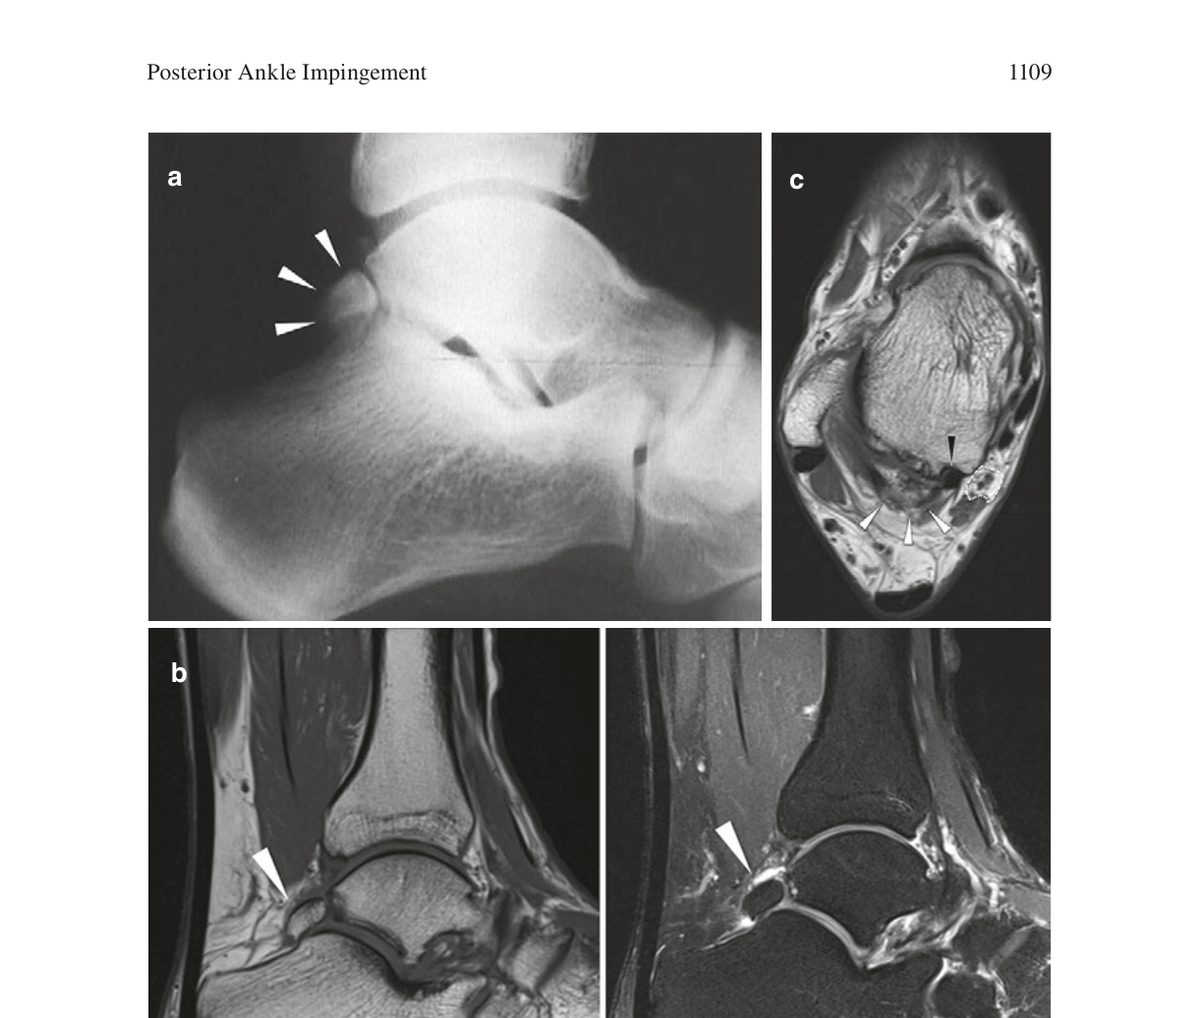

МРТ - оптимальный метод визуализации при PAI. Стандартный протокол включает сагиттальные T1-взвешенные изображения и последовательности с подавлением жира (PDW с жироподавлением или STIR).

Костные изменения: отёк костного мозга в os trigonum или процессе Штиды и прилежащих отделах таранной кости, жидкость в зоне синхондроза (при os trigonum). Отёк костного мозга - наиболее надёжный МРТ-признак симптоматического os trigonum, в отличие от простого наличия добавочной косточки.

Мягкотканные изменения: выпот в заднем завороте сустава, ганглионарные кисты, утолщение синовиальной оболочки, теносиновит FHL (жидкость во влагалище сухожилия, утолщение синовиальной оболочки влагалища).

МРТ также позволяет оценить состояние задних связок голеностопного сустава, выявить остеохондральные повреждения блока таранной кости и исключить другие причины задней боли - в частности, инсерционную тендинопатию ахиллова сухожилия и ретрокальканеальный бурсит.

Рис. 1. МРТ заднего отдела голеностопного сустава при синдроме os trigonum: (a) сагиттальный срез - os trigonum (стрелки); (b) сагиттальные T1- и T2-взвешенные изображения; (c) аксиальный срез - os trigonum (белые стрелки), сухожилие FHL (чёрная стрелка), сосудисто-нервный пучок (пунктирная линия). Адаптировано из Wagner, 2022